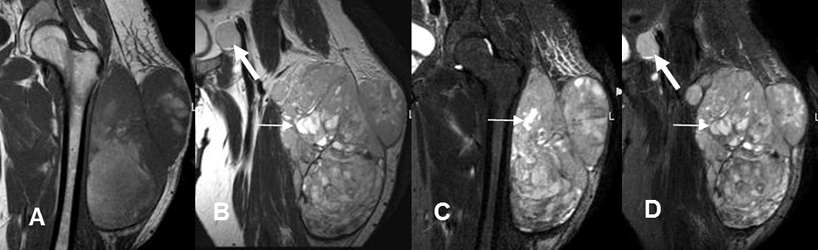

Fig 199 B. Sarcoma sinovial.

A: RM coronal en T1, B: RM coronal en T2, C y D: RM coronal en STIR. Igual paciente anterior. Lesión de tejidos blandos de predominio sólido, aunque con algunas áreas quísticas. (Flechas delgadas). No ocasiona compromiso óseo y se asocia con adenopatía inguinal. (Flechas gruesas).